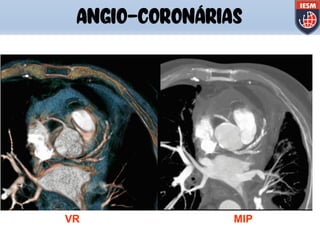

ANGIO-CORONÁRIAS

Programa de pós processamento de

imagem que isola o coração das

outras estruturas, reconstruindo-o

em 3D, onde é possivel visualizar a

anatomia cardiaca, artéria e veia

coronária, anomalias congênitas,

cavidades do coração, enxerto,

Stents e o completo sistema

vascular.

CardIQ

(Analisys)

q Programa é usado para calcular

e exibir variações anatômicas e

funcionais do coração.

q Pode-se quantificar o volume

ventricular esquerdo e direito assim

como volume do miocárdio,

endocárdio e epicárdio

q É necessário somente uso de

contraste EV para se poder fazer a

análise cardíaca funcional.

(Function)

3D

Epicárdio e Endocárdio

q Método não invasivo que

mede quantitativamente a

extensão do depósito de cálcio

na Artéria Coronária.

SmartScore

(Cardiac CT)

VR MIP